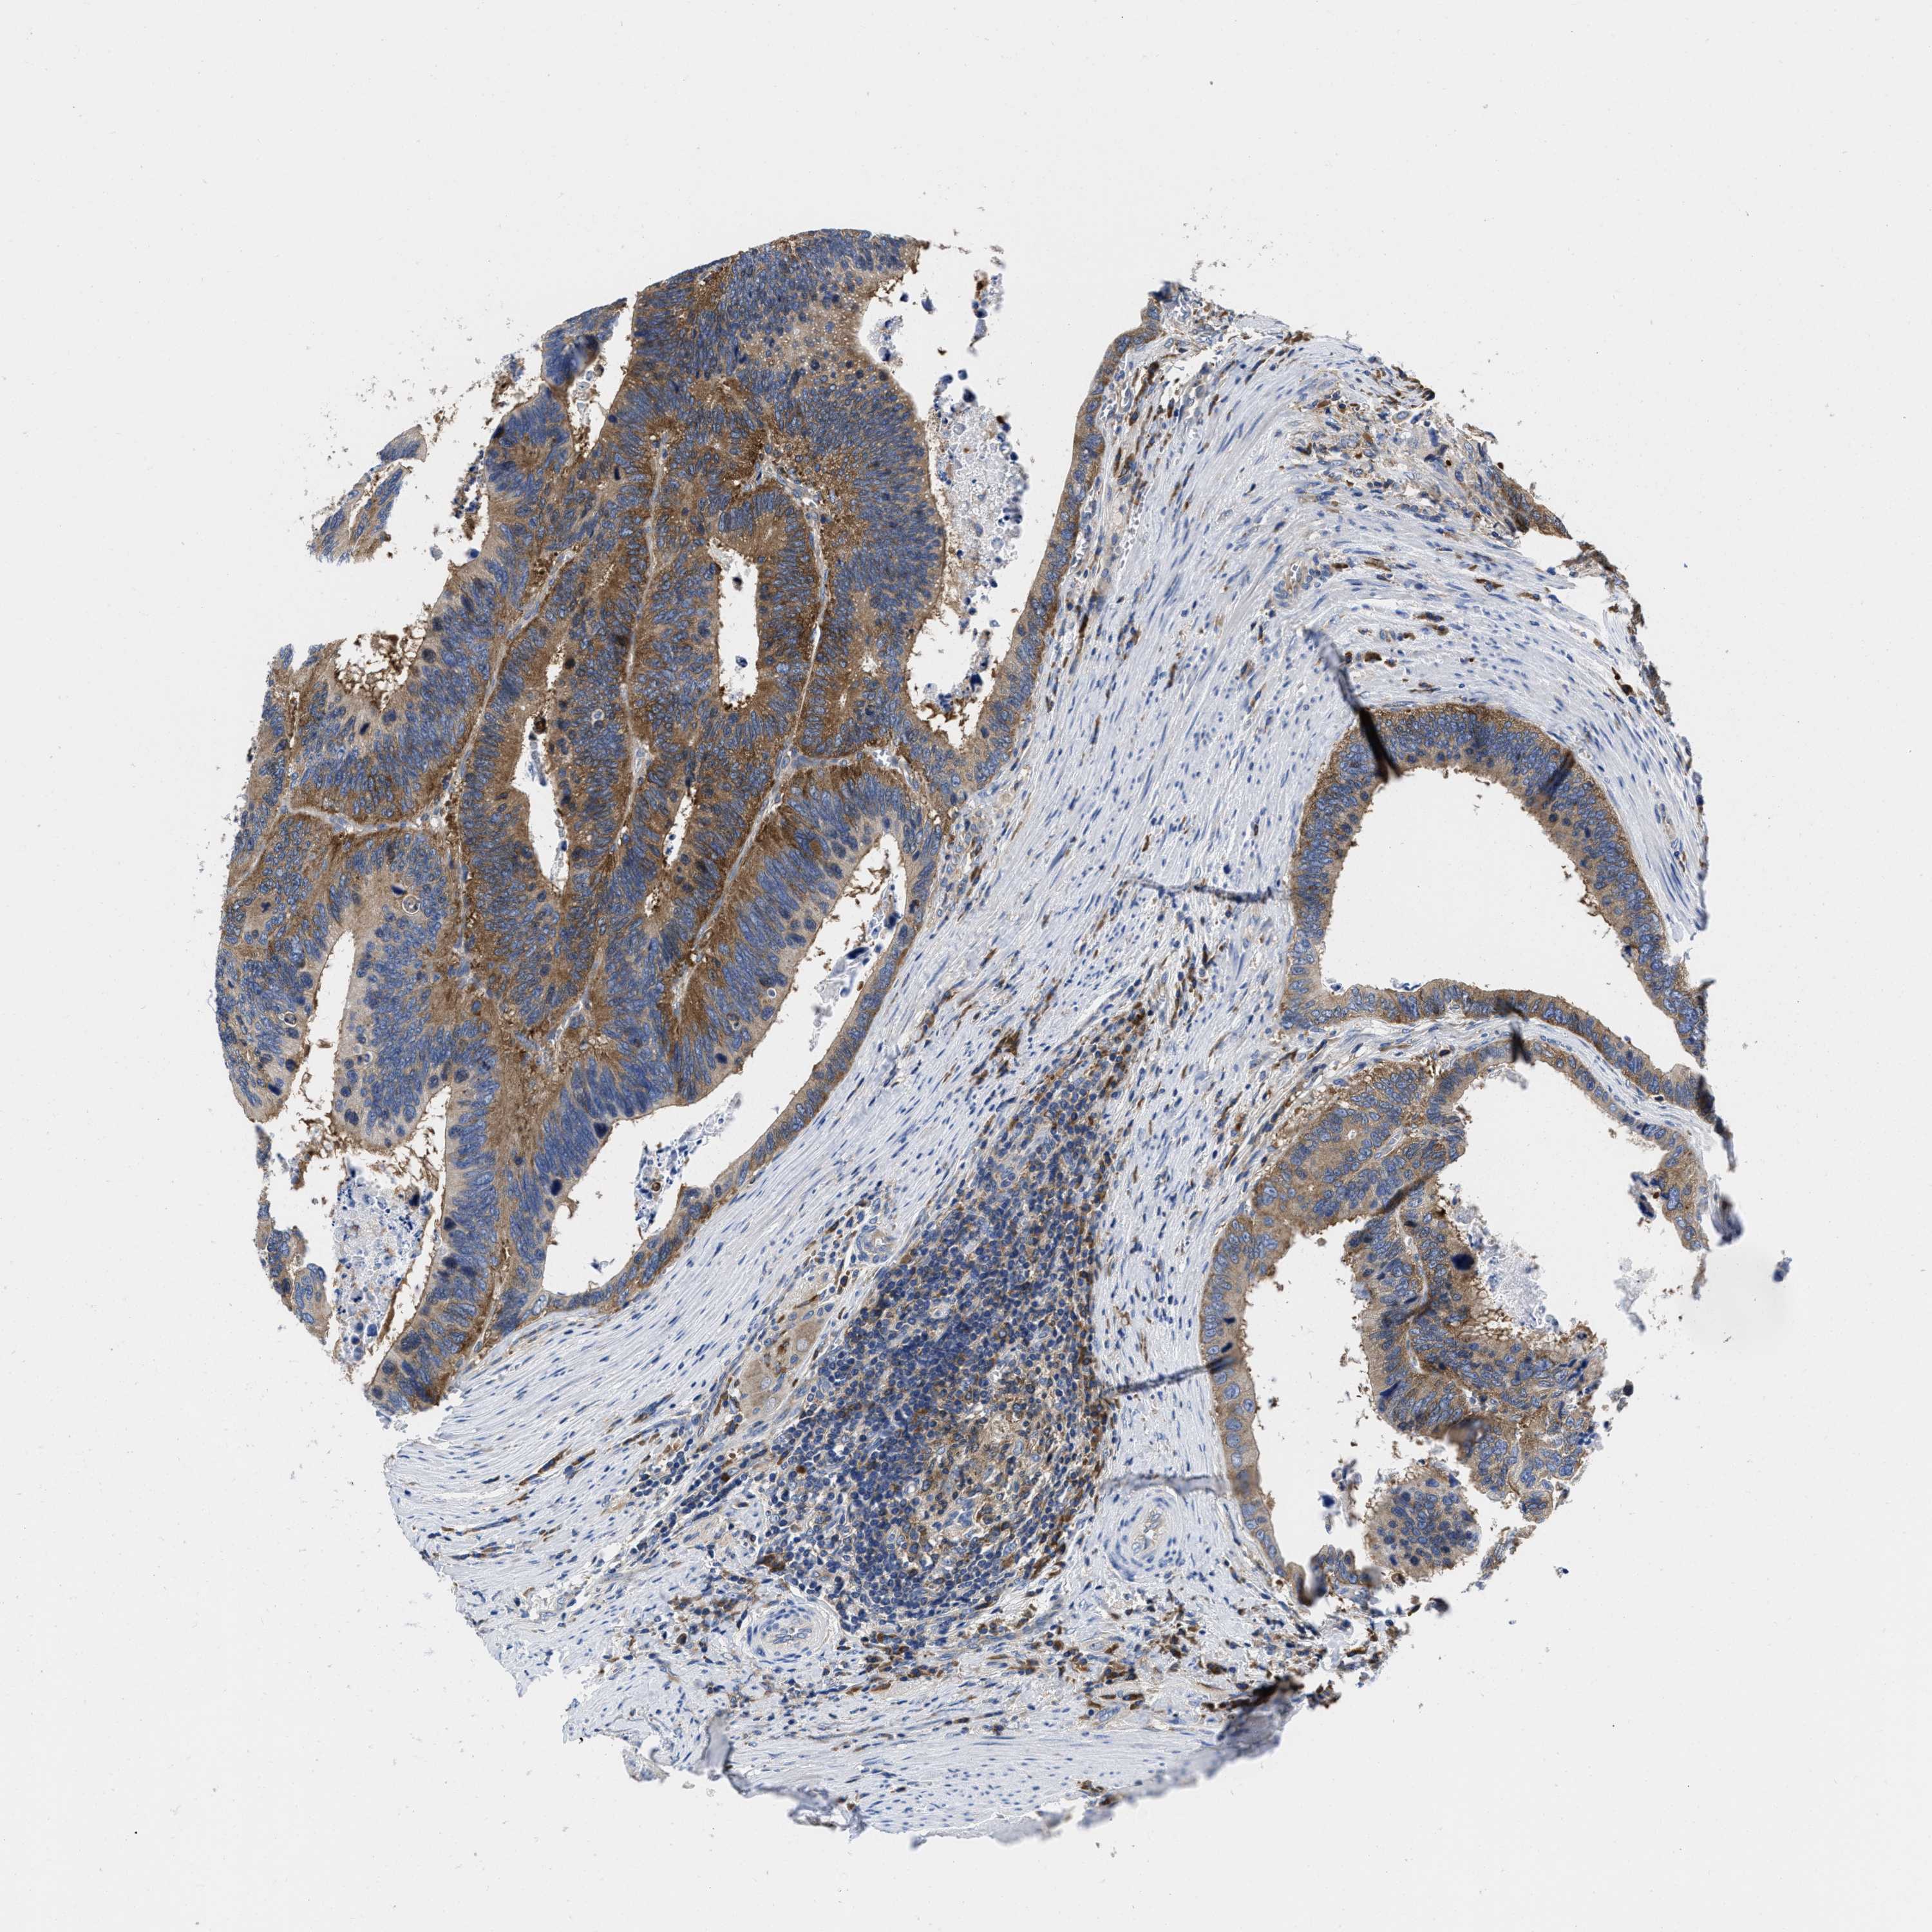

CANCER COLORECTAL CANCER Show tissue menu

Colorectal cancer

Rectum adenocarcinoma